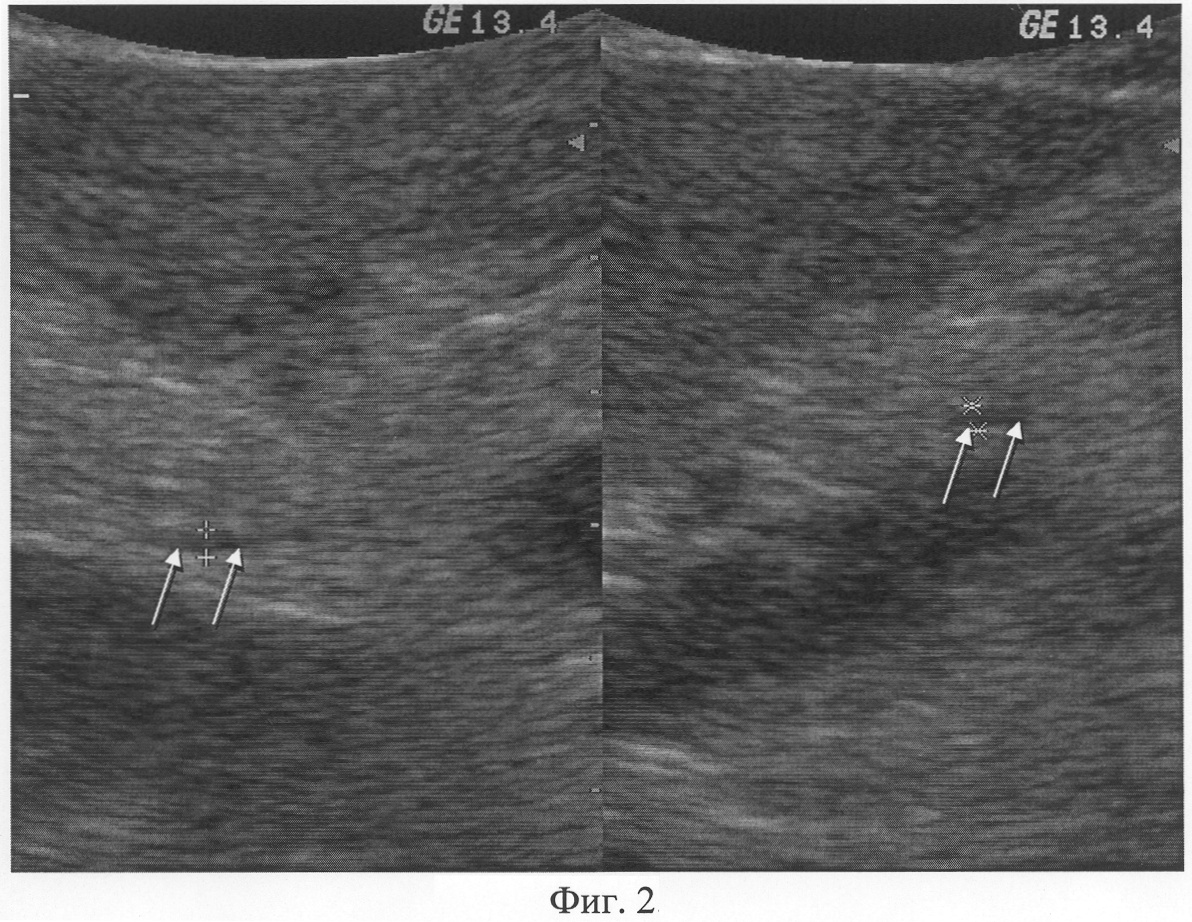

При отсутствии повышения эхогенности содержимого просвета главного панкреатического протока в сравнении с исходным состоянием вследствие отсутствия заполнения контрастным веществом главного панкреатического протока определяют отсутствие дуоденопанкреатического рефлюкса, как показано на Фиг.2.

При осуществлении ультразвукового исследования согласно предлагаемому способу, были выявлены следующие параметры. Исходно: в просвете главного панкреатического протока на всем протяжении визуализируется однородное анэхогенное содержимое; просвет нисходящего отдела двенадцатиперстной кишки умеренно дилятирован, содержимое неоднородное за счет крупнодисперсной гиперэхогенной взвеси. Осмотр после контрастирования: максимальный диаметр просвета поперечного сечения двенадцатиперстной кишки составляет 25 мм, в ее просвете определяется однородное гиперэхогенное содержимое (контрастное вещество); в просвете дистального отдела главного панкреатического протока определяется однородное гиперэхогенное содержимое (контрастное вещество). Заключение: Дуоденопанкреатический рефлюкс (фиг.2).